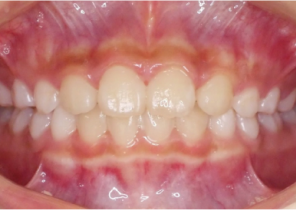

Étude de cas 1

10 ans et 0 mois, 18 étapes d’appareils d’expansion palatine Invisalign

Avec l’aimable autorisation de la Dre Sandra Khong Tai

Avant le traitement d’expansion avec les appareils d’expansion palatine Invisalign

Après le traitement d’expansion avec les appareils d’expansion palatine Invisalign

Après le traitement Invisalign First